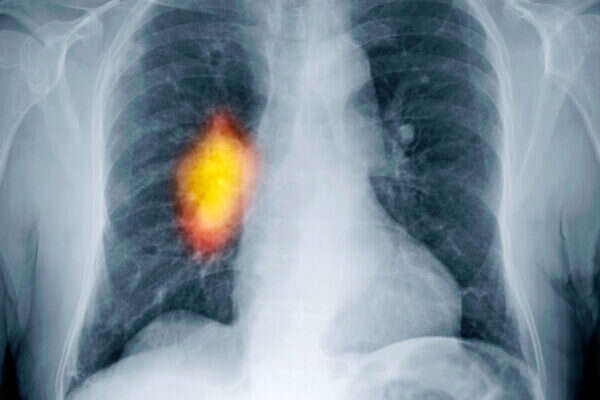

כ־2,000 חולים חדשים בסרטן ריאות מתגלים בישראל בכל שנה, אך כעת תרופה ייחודית מעניקה להם תקווה: היא נקראת "אפטיניב", והמחקרים מראים שהיא מצליחה לבלום את המחלה הקטלנית ולשפר את איכות חייהם של החולים.

אפטיניב, של חברת התרופות הגרמנית "בורינגר אינגלהיים", מסווגת כטיפול ביולוגי שמצליח לעכב את פעילותם של חלק מהחלבונים שמביאים להתפתחות הגידול הסרטני. בשלב זה, התרופה אינה מיועדת לכל חולי סרטן הריאות, אלא רק לחלקם, בהתאם לסיווג המוטציה הגנטית של המחלה כפי שאובחנה אצל החולה. עם זאת, ההערכה היא שבהמשך תתאים התרופה לסוגים נוספים של סרטן הריאות ואף למחלות סרטן נוספות.

לאחרונה אושרה אפטיניב לשימוש על ידי רשויות הבריאות בארה"ב ובאירופה, לאחר שמחקרים הציגו נתונים מעודדים. כך, למשל, חולים שטופלו בה חיו זמן רב יותר - כשנה - ללא צמיחה של הגידול, בהשוואה לחולים שקיבלו טיפול כימותרפי סטנדרטי וחיו רק מחצית מהזמן ללא צמיחה של הגידול. נוסף על כך, החולים שנטלו את התרופה דיווחו על שיפור משמעותי באיכות חייהם ועל צמצום תופעות המחלה.